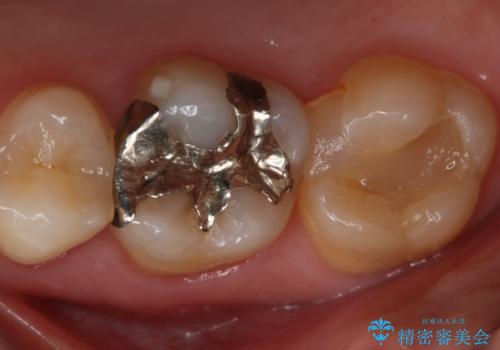

- 右上大臼歯の再治療を希望され来院された患者様です。

切削量と形状を考慮し、インレーでの治療を計画しました。

患者様がゴールドを希望されたのでゴールドインレーを選択しました。